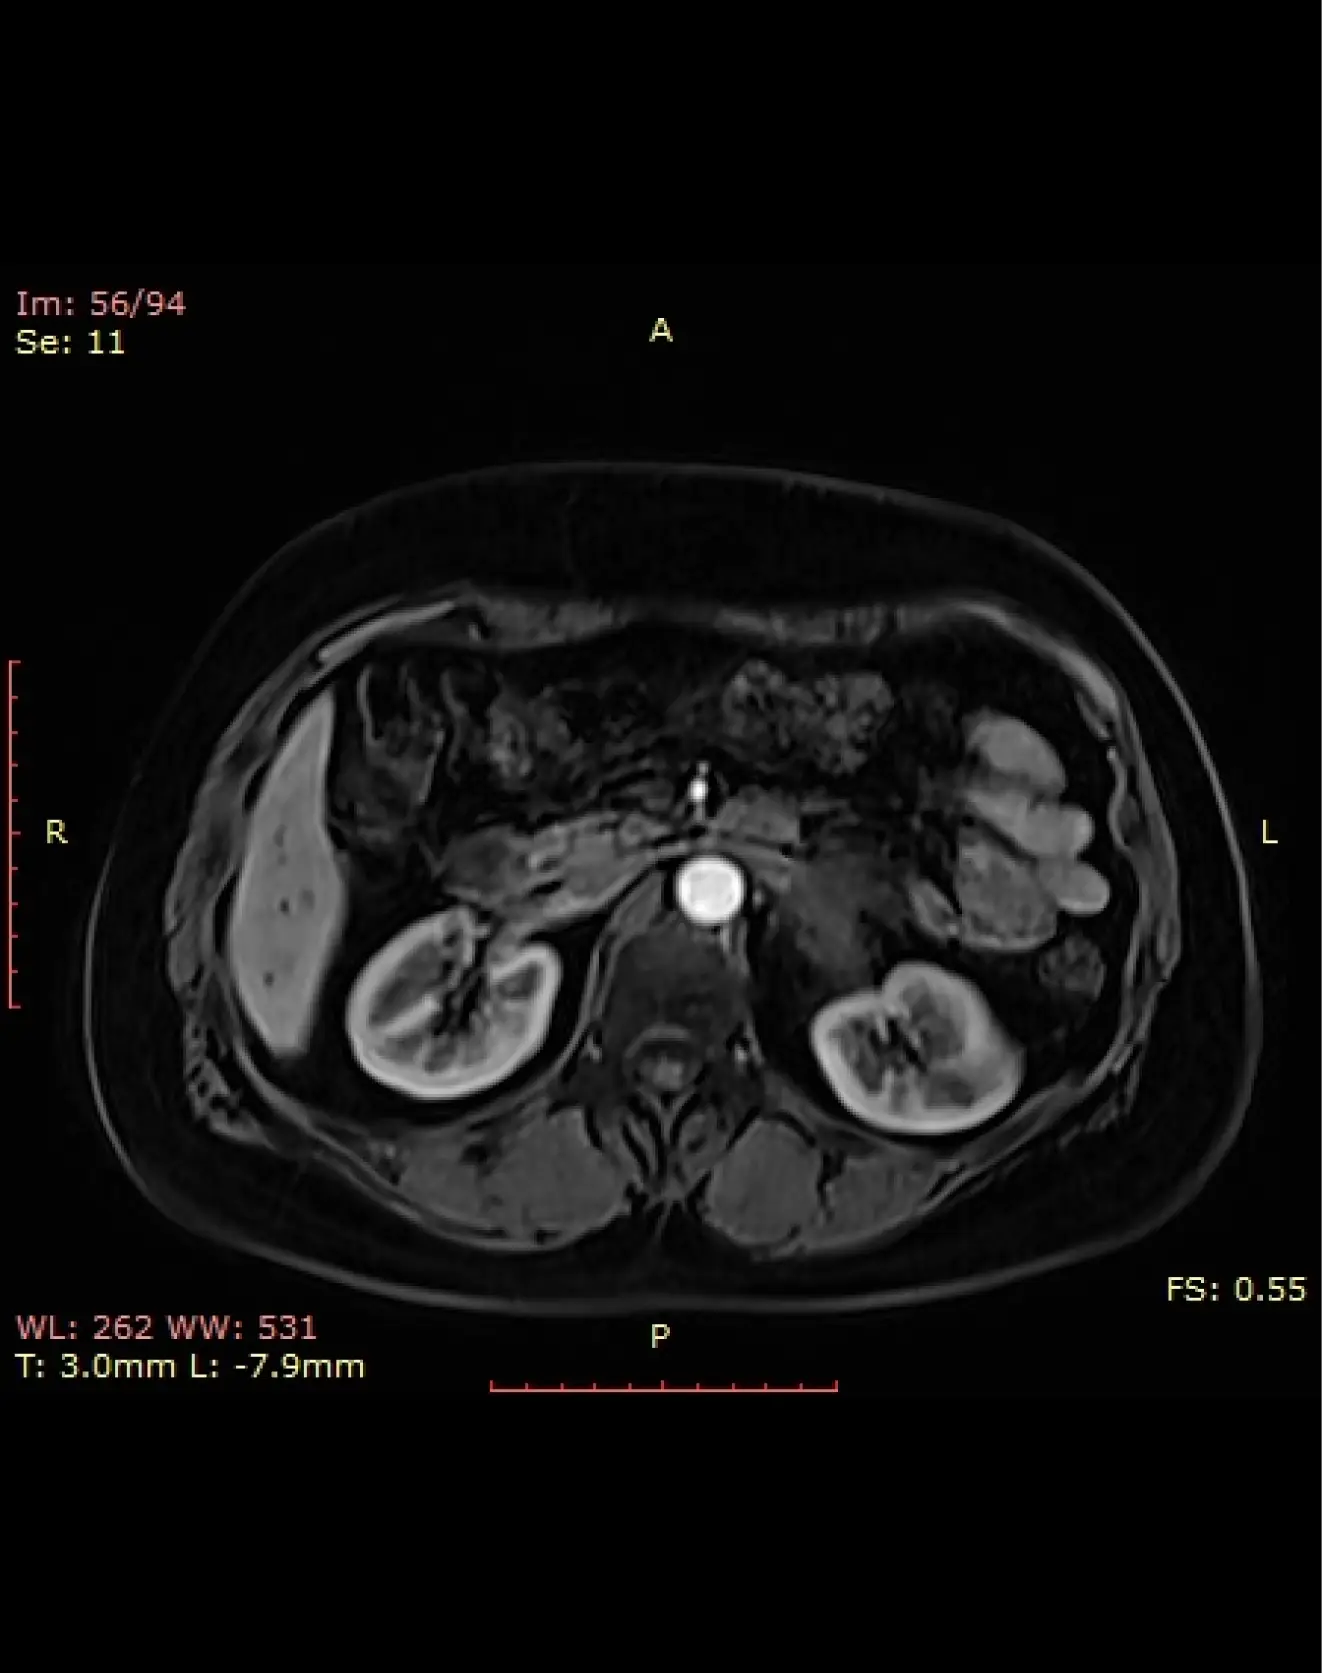

Исследование с контрастом - Примавист (ОБП, оценка печени)

Primovist (Примавист) — это специализированное контрастное вещество, предназначенное для исследования печени.